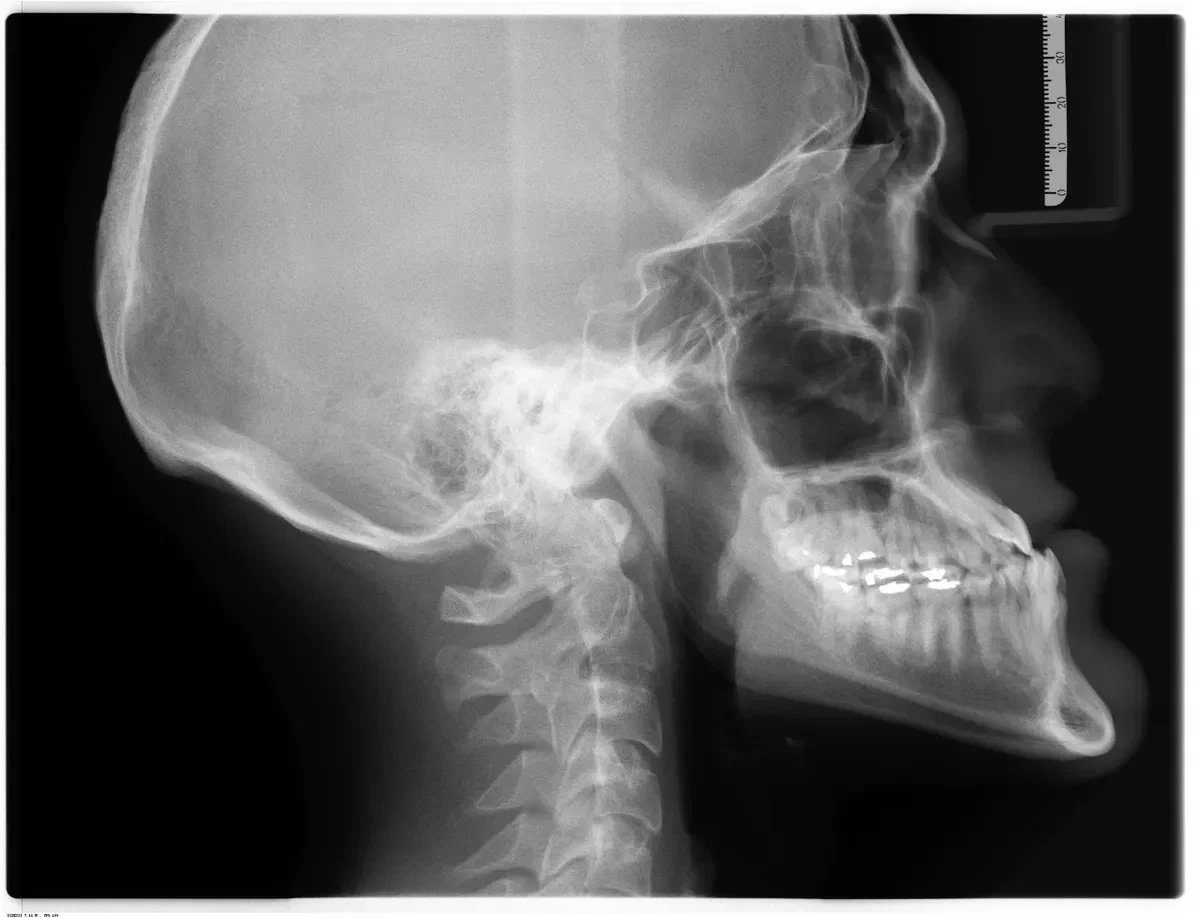

Zygomatic dental implants are an advanced implant technique used when severe bone loss in the upper jaw prevents placement of traditional implants. Instead of anchoring in the maxilla, zygomatic implants engage the zygomatic bone (cheekbone), which offers dense, stable support.

Placement requires precise 3D planning and careful avoidance of critical anatomy such as the sinus and orbit.